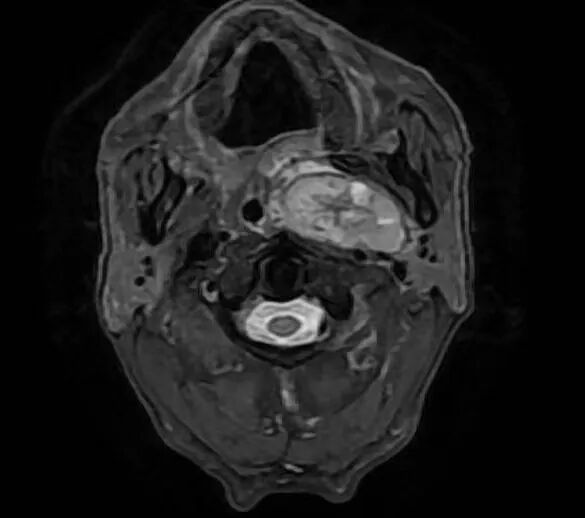

??患者入院后完善颈部MR示:左侧咽旁间隙见卵圆形等T1,长T2信号,增强扫描不均匀强化,病灶最大截面积5.0cm×2.3cm。左侧咽腔明显受压变窄。